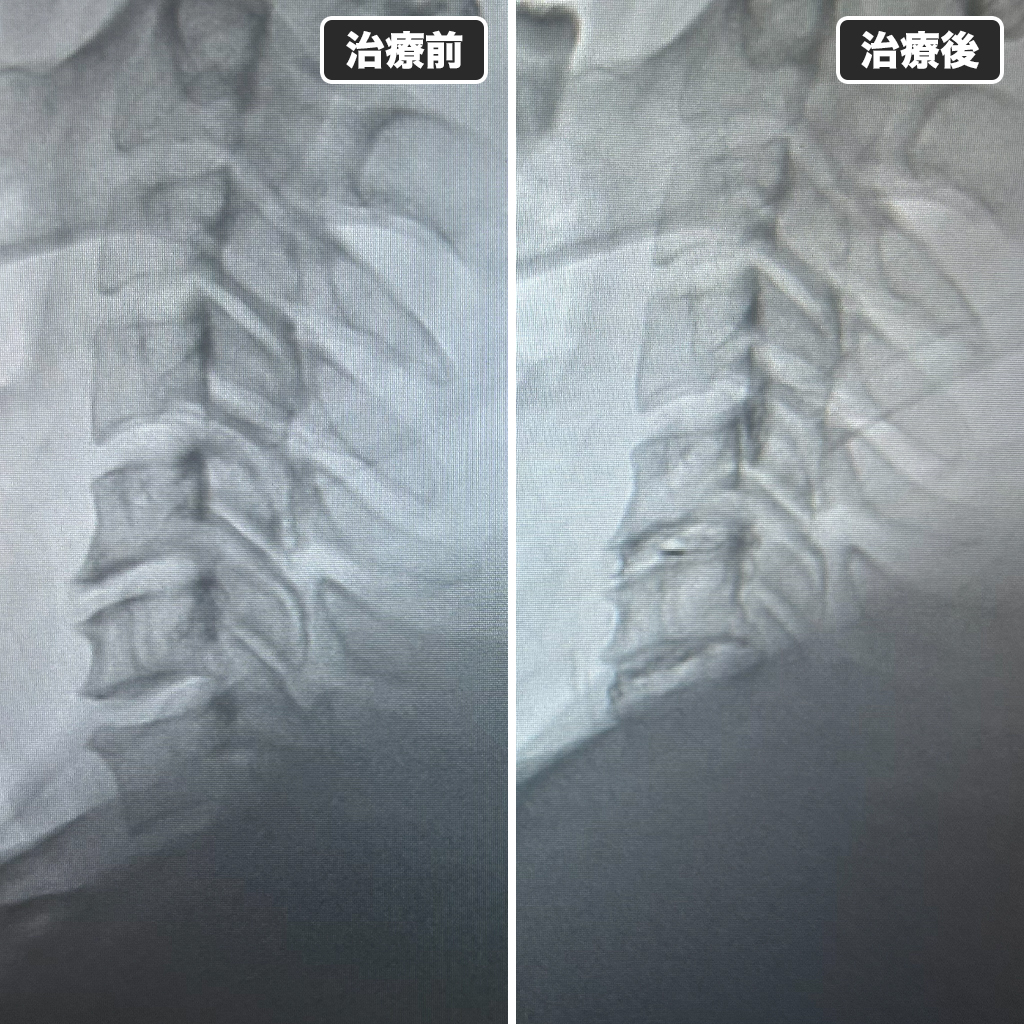

治療前後のレントゲン写真

治療前後のレントゲン写真になります。左側が治療前で右側が治療後になります。